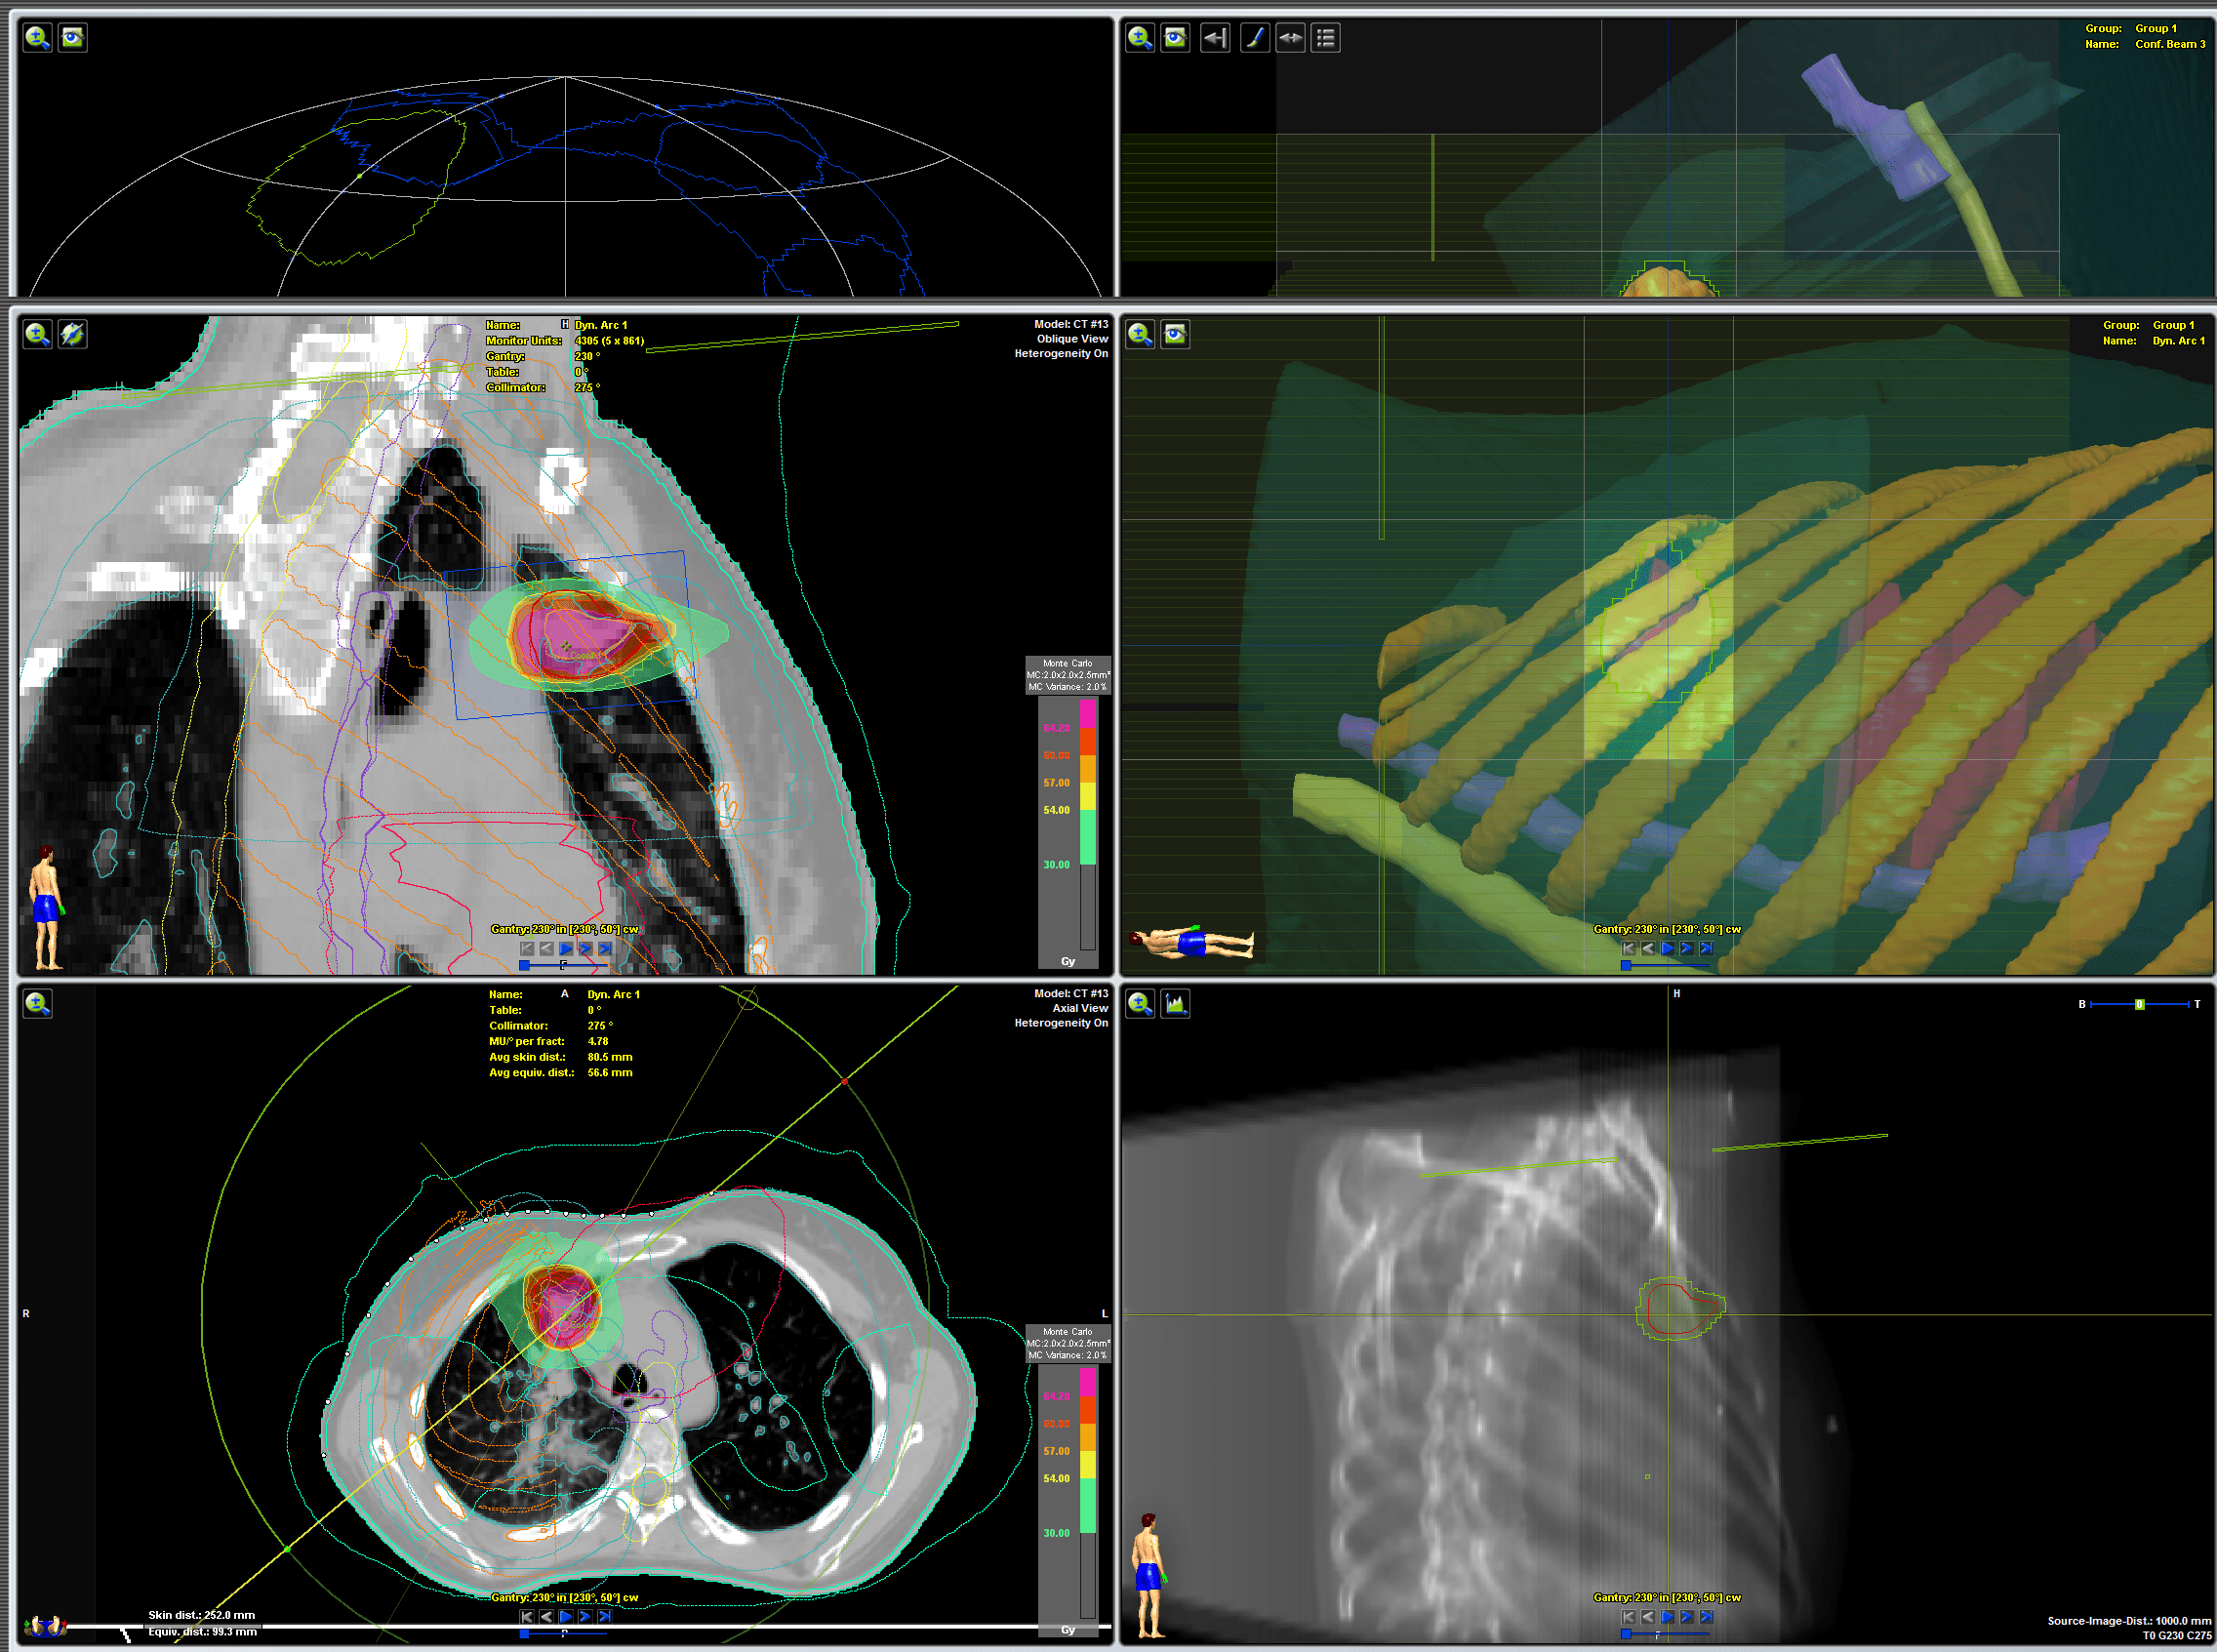

Planeación virtual de tumor en pulmón

Planeación virtual de tumor en pulmón. Físicos médicos y dosimetristas han delimitado los volúmenes blancos y los órganos de riesgo (tejidos sanos circundantes) y calculado la distribución de dosis precisas.

tradiografía de tumor en el pulmón.